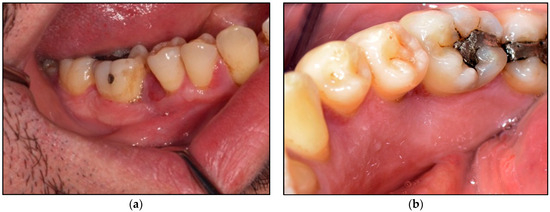

2.2.1. Clinical Examination

2.2.2. Investigations